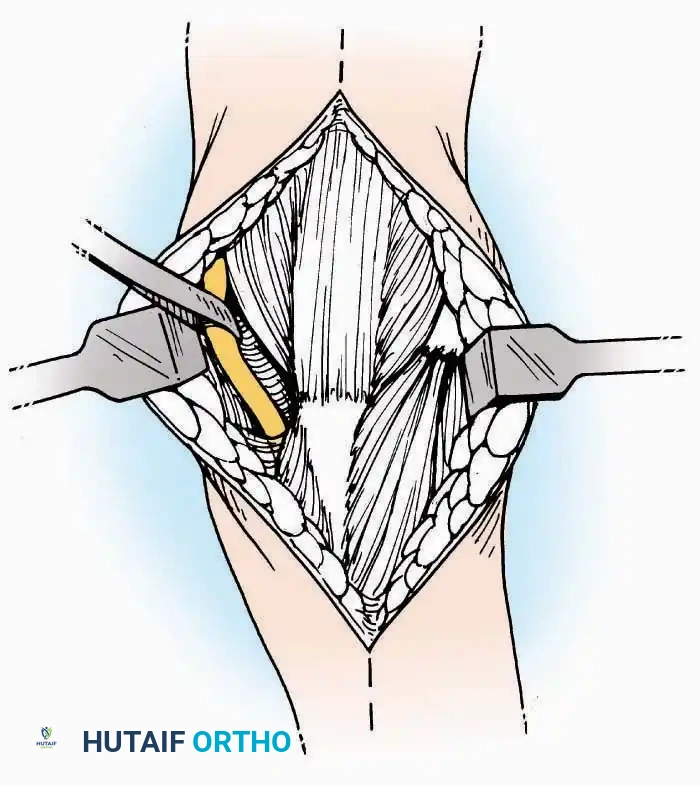

Anterior Approach

Indications: Total ankle arthroplasty (TAA), anterior ankle arthrodesis, and excision of anterior tibial/talar osteophytes (anterior impingement).

Surgical Technique:

* Incision: Make a 10 to 15 cm longitudinal incision over the anterior aspect of the ankle, centered exactly midway between the medial and lateral malleoli.

* Superficial Dissection: Incise the superficial fascia. Identify and protect the superficial peroneal nerve branches laterally and the saphenous nerve medially.

* Internervous Plane: The deep dissection exploits the plane between the Extensor Hallucis Longus (EHL) tendon (innervated by the deep peroneal nerve) and the Extensor Digitorum Longus (EDL) tendons (also innervated by the deep peroneal nerve).

* Neurovascular Bundle: Incise the extensor retinaculum. Carefully identify the anterior tibial artery and the deep peroneal nerve, which typically lie between the EHL and EDL, or directly deep to the EHL. Retract the neurovascular bundle laterally with the EDL, or medially with the EHL, depending on the specific anatomical variant encountered (lateral retraction is most common).

* Capsulotomy: Incise the anterior joint capsule longitudinally. Elevate the capsule subperiosteally from the anterior tibia and the talar neck to expose the entire tibiotalar articulation.